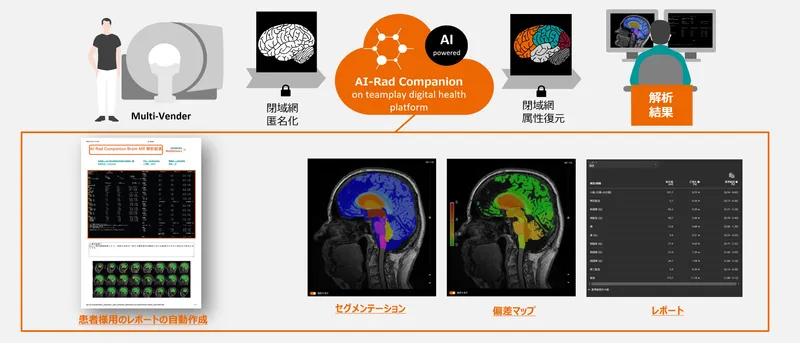

脳に対するMR画像診断支援として転送された画像からAIアルゴリズムにより自動的に脳の形態解析を実行し、結果を出力。

本ソフトウェアはクラウド(またはオンプレミス)環境で頭部MR画像から脳の各部位を自動的にセグメンテーションし、部位ごとの体積を自動計測します。 また白質の高信号領域の自動検出機能も備わっています。

サービスの特長

AI-Rad Companion Brain MRは後処理用の画像解析ソフトウェアで、臨床医による脳MR画像の表示、解析および評価を支援します。 以下の各種機能が備わっています。 ・各脳構造の自動セグメンテーションと定量解析 ・各脳構造の健常者集団から得た基準データとの定量比較 ・白質の高信号領域の自動検出機能 ・レポート作成のための結果表示(数値及び視覚化情報をすべて含む)

MPRAGE画像シリーズでの使用になります。またシリーズが非造影で撮像されている必要があります。 推奨スキャンパラメータに関してはお問い合わせください。 本ソフトウェアは医師の読影を補助する医療機器プログラムであり、診断を行う医療機器プログラムではありません。そのため、診断は医師の責任において行ってください。